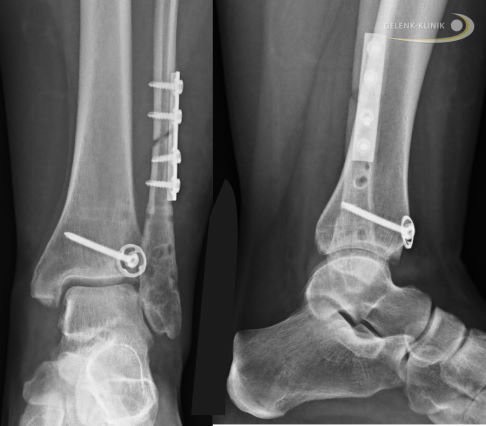

Weiterhin ist eine frühzeitige Abklärung von weiteren Knochen- und Weichteilverletzungen im Rahmen von Sprunggelenksfrakturen oder einer Maisonneuve-Verletzung wichtig. Bei einer Weber-C-Sprunggelenksfraktur mit gleichzeitiger Verletzung von Wadenbein und Syndesmoseband erfolgt in der Regel der Einsatz eines Implantats in einer Osteosynthese.

Bei der Erstversorgung einer Maisonneuve-Verletzung, bei der das Syndesmoseband, die Membrana interossea cruris und das Volkmann-Dreieck verletzt sind, werden in der Gelenk-Klinik häufig stabilisierende Stellschrauben eingesetzt. Wir belassen die Stellschrauben wie auch die Schrauben nach Osteosynthese für mindestens 8 Wochen im Sprunggelenk.

Auch die primäre Versorgung der Maisonneuve-Verletzung mit guter Einstellung der Fibula ist elementar bei ausgeprägter Instabilität. Hier werden häufig 2 stabilisierende Träger verwendet. Bei der Weber C-Fraktur mit gleichzeitiger Syndesmosenverletzung wird oft nur ein Implantat verwendet. Vorteile der statischen Schraubenfixierung im Vergleich zur dynamischen Behandlung sind bei wissenschaftlichen Untersuchungen bisher nicht festgestellt worden.

Zunehmend belassen die Spezialisten der Gelenk-Klinik die implantierten Stellschrauben nach Syndesmosenverletzung auch nach der 8. Woche. Die längere Stabilisierung ergibt bei den schweren Verletzungen des Sprunggelenkgabel insgesamt eine bessere Heilungschance.